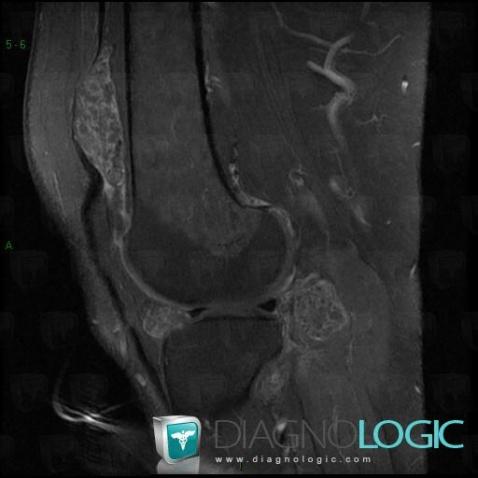

Ostéochondromatose synoviale, Articulations fémoro tibiales / Echancrure, IRM

Voici les informations spécifiques à l'image clé ci dessus:

- Diagnostic Ostéochondromatose synoviale, Localisation(s) Articulations fémoro tibiales / Echancrure, comportant les gammes Masse ou épaississement synovial, Masse des parties molles juxta articulaires, Arthropathie avec nodules des parties molles